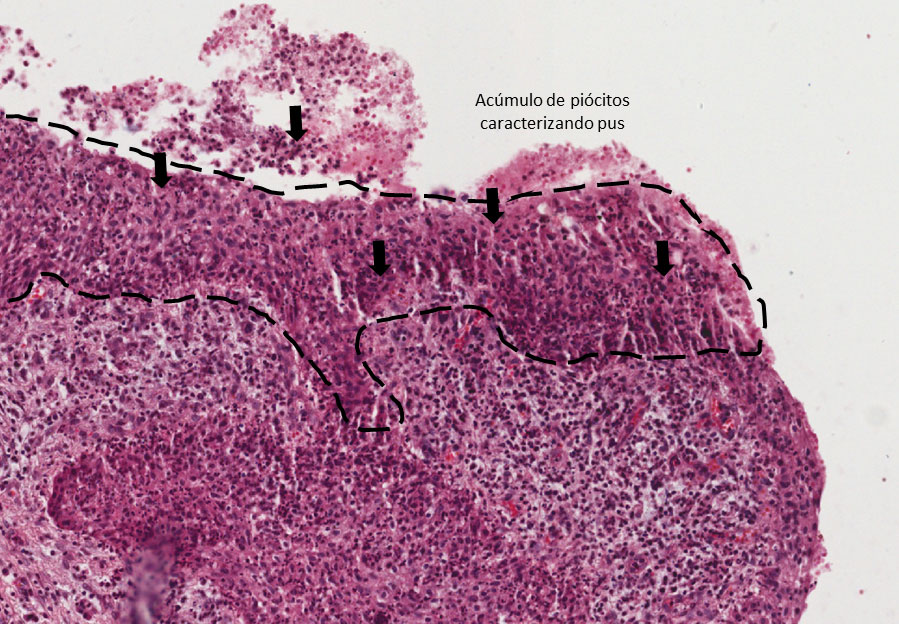

Cavidade (lúmen) contendo piócitos (pus), tecido conjuntivo contendo neutrófilos, infiltrado inflamatório linfoplasmocitário (asterisco amarelo) e vasos de neoformação, externamente cápsula fibrosa, caracterizando tecido de granulação. (Figura 1)

Observar a cavidade virtual, contendo pus (piócitos — Figura 2 — área tracejada em preto e setas), circundada por tecido de granulação apresentando infiltrado inflamatório contendo plasmócitos (asterisco amarelo-Figura 3) linfócitos (asterisco verde), neoformação vascular e fibroplasia (seta A — Figura 3). Na periferia observa-se uma maior deposição de fibras colágenas caracterizando uma cápsula fibrosa.

Abscesso Apical Crônico